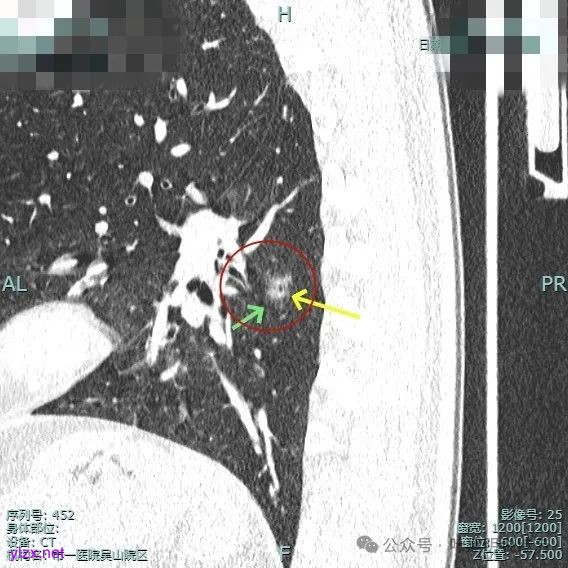

主病灶位于下叶后基底段下肺静脉水平,次病灶在同一层面位靠外基底段交界附近。

薄层上看主病灶不纯,有实性成分,也有血管穿行;次病灶是纯磨,微小的结节,但轮廓与边界较为清楚。

主病灶有血管进展与异常增粗,灶内有实性成分,中间有小空泡征。

进入病灶内的血管壁毛糙不平,有异常增粗。

血管进入且异常增粗,其余部分密度为磨玻璃及少许点状偏高成分。